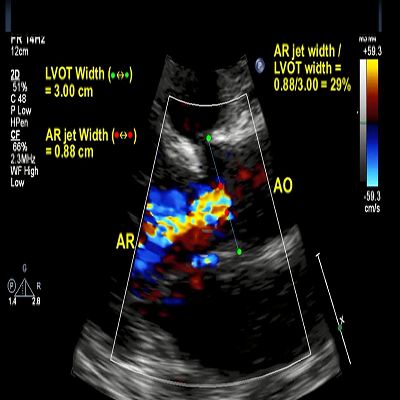

Color Doppler examination aortic valve

419 KB

Mild AR

489 KB

Mild aortic regurgitation

470 KB

Mild aortic regurgitation

765 KB